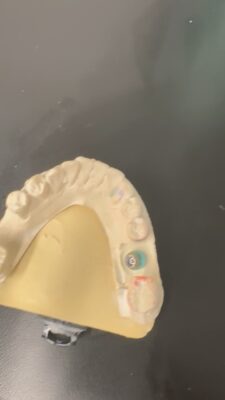

The case I am sharing has been quite challenging for me restoratively. Patient was referred out for implant placement #31. It is a Nobel implant WP. First time I restored it, within a week of insert abutment fractured. Fortunately, retrieving the abutment screw was not that difficult. When I inserted the first time I did know something is…

This one is a bit tough. I say that because it looks like it was a little difficult on the surgical aspect with minimal bone height. It always seems to work out this way–in the cases where you wish to have no problems, you often encounter them.

It’s okay though. Let’s try to get to the bottom of this.

First: I understand you cemented the crown…